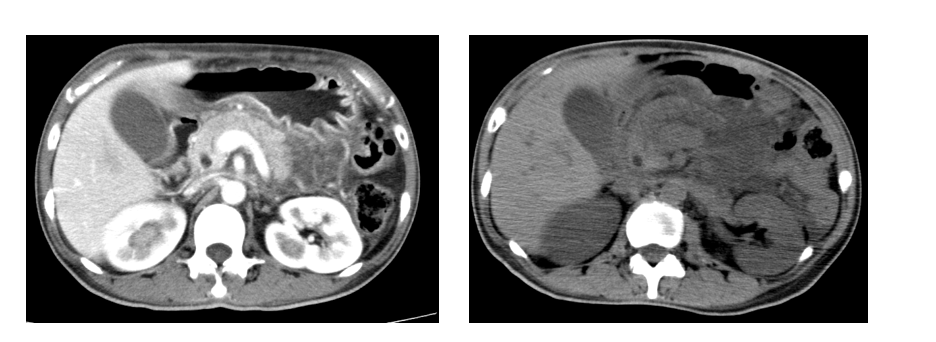

胰腺CT平扫+增强示:胰腺形态饱满,伴周围渗出改变,符合急性胰腺炎改变。入院查体发现患者面容较其身份证照片有显著变化,表现出典型的肢端肥大症样特征。进一步检测显示GH水平升高,IGF-1初次检测正常。在积极纠正酮症酸中毒与急性胰腺炎后,行垂体核磁共振(MRI)检查,发现垂体大腺瘤。

该病例为一名43岁女性患者,因突发意识模糊、恶心、呕吐18小时入院。入院后查体发现患者面容较其身份证照片明显改变,呈典型肢端肥大症特征。CT显示胰腺形态饱满并伴周围渗出,符合急性胰腺炎表现。进一步内分泌检查发现GH水平升高,初次IGF-1检测正常。经纠正糖尿病酮症酸中毒与胰腺炎后行垂体MRI,确诊为生长激素型垂体大腺瘤。为降低手术风险、改善代谢状态,术前给予长效奥曲肽微球治疗3个月,复查显示肿瘤体积缩小、症状显著改善,随后成功行垂体瘤切除术,术后恢复良好。